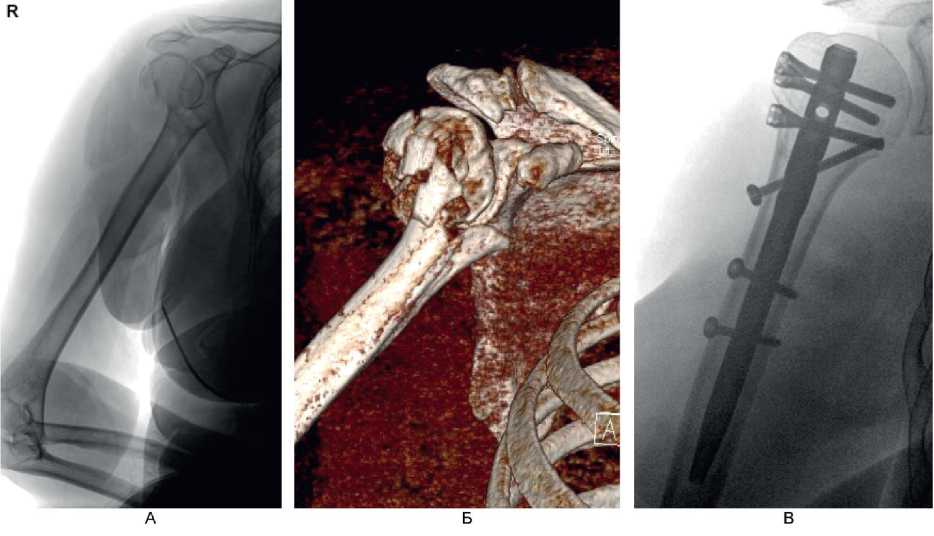

Клинический пример 2. Больной А., 50 лет, поступил в клинику ВЦЭРМ им. А.М. Никифорова в экстренном порядке. Выполнены рентгенография плечевого сустава в стандартных проекциях (рис. 8А), и компьютерная томография (см. рис. 8Б).

Рис. 8. Больной А., 50 лет. А – рентгенография плечевого сустава в стандартных проекциях; Б – компьютерная томография до операции

Перелом по классификации АО – С3.1. На 2-е сутки после поступления выполнено оперативное вмешательство – БИОС хирургической шейки правой плечевой кости. Рентгенография на 1-е сутки после операции представлена на рис. 9А, Б, контрольная рентгенография плечевого сустава через 6 мес после операции – на рис. 9В. Функциональный результат после операции – на рис. 10.